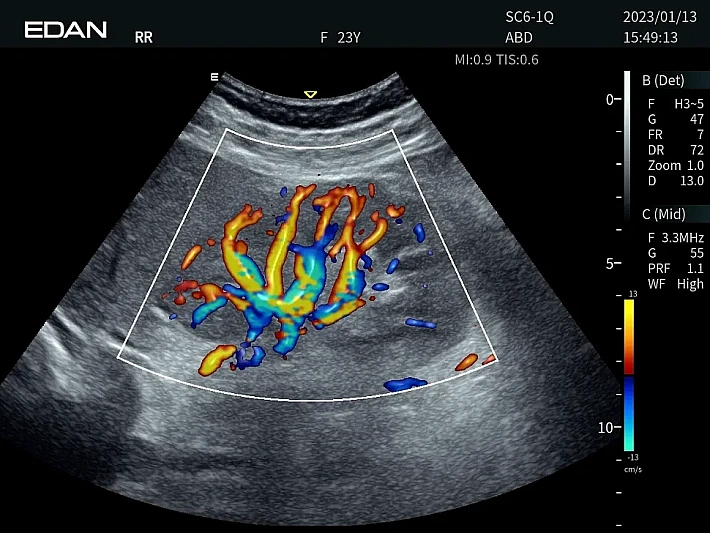

Медицинское оборудование и сервисное обслуживание